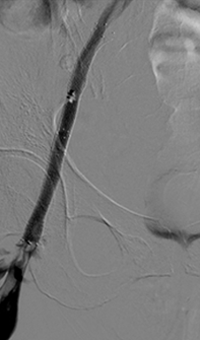

Acute DVT left lower extremity revascularization

47 year old male presented with leg swelling ~2 weeks.

Procedural steps

• Power Pulse delivery of 10mg tPA followed by

• 20 minute dwell time

• Total runtime was 300 seconds

Acute DVT Left Lower Extremity Revascularization pre-treatment angio.

Acute Iliofemoral thrombus pre-treatment

IVC Filter placed (left image)

Acute DVT Left Lower Extremity Revascularization post-treatment.

Post ZelanteDVT  pharmacomechanical thrombectomy

Case images courtesy of David Wilson M.D. – Harbin Clinic, Rome, Georgia – December 19, 2015